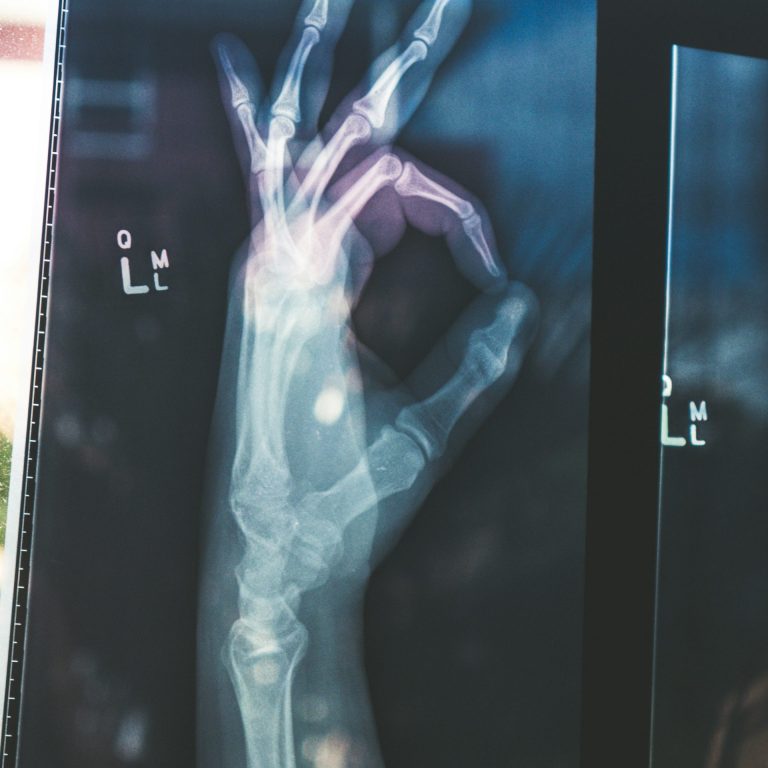

Our private practice is equipped with the latest technology.